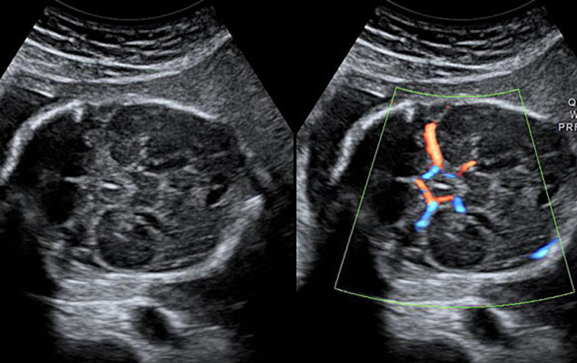

产科_胎儿颅脑_大脑基底动脉环